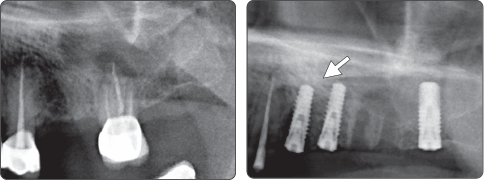

Рекомендуется использовать сверло для синус-лифтинга и уплотнительную фрезу вместе

1. Синус-лифтинг (имплантат Ø4.0)